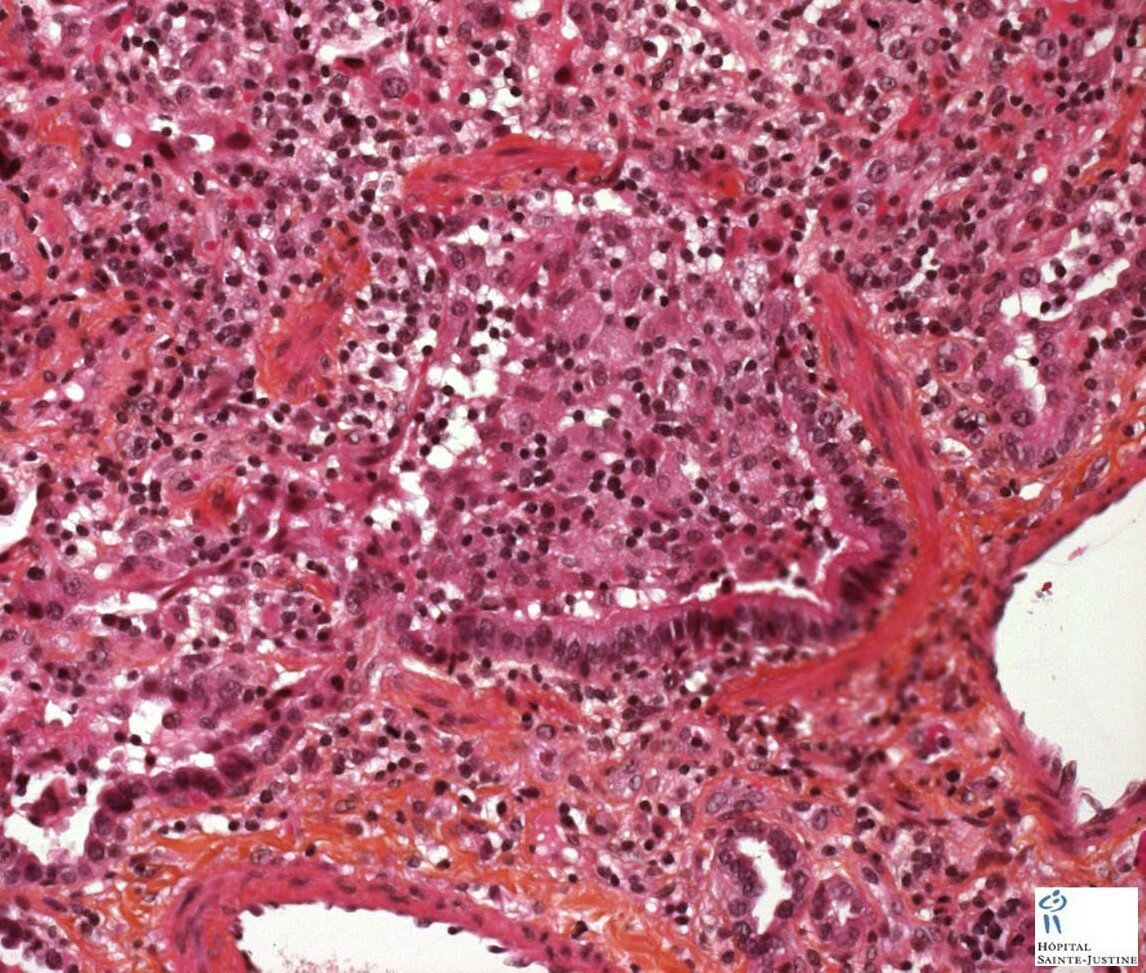

necrotizing bronchiolitis